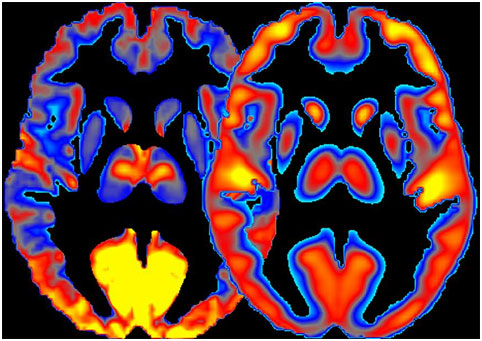

我們先來看張圖,這是酗酒者和健康人的對(duì)比圖。

“在酗酒者的大腦中,我們看到,丘腦、感覺通道和大腦的額葉皮質(zhì)等部分活躍程度不高,而這些部位對(duì)作決策很重要。這是由于長期接觸酒精對(duì)腦細(xì)胞產(chǎn)生的毒性作用。”研究者說。這意味著,酒精嚴(yán)重影響了酗酒者的決策能力。

研究人員還發(fā)現(xiàn),酗酒后大腦視覺區(qū)域的功率下降,這與視覺神經(jīng)傳輸?shù)闹袛嘤嘘P(guān)。同時(shí),在酒精中毒期間,視覺區(qū)域的消耗下降的最為顯著,這與這些區(qū)域?qū)μ娲芰?如酒精代謝的副產(chǎn)物乙酸鹽)的依賴是一致的。

基于此,他們得出結(jié)論:與輕度飲酒者相比,重度飲酒者的葡萄糖代謝效率普遍較低,使大腦轉(zhuǎn)向低效的能量利用狀態(tài)。但具體機(jī)制還有待進(jìn)一步研究。